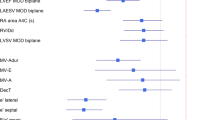

Machine learning techniques designed to recognize views and perform measurements are increasingly used to address the need for automation of the interpretation of echocardiographic images. The current study was designed to determine whether a recently developed and validated deep learning (DL) algorithm for automated measurements of echocardiographic parameters of left heart chamber size and function can improve the reproducibility and shorten the analysis time, compared to the conventional methodology. The DL algorithm trained to identify standard views and provide automated measurements of 20 standard parameters, was applied to images obtained in 12 randomly selected echocardiographic studies. The resultant measurements were reviewed and revised as necessary by 10 independent expert readers. The same readers also performed conventional manual measurements, which were averaged and used as the reference standard for the DL-assisted approach with and without the manual revisions. Inter-reader variability was quantified using coefficients of variation, which together with analysis times, were compared between the conventional reads and the DL-assisted approach. The fully automated DL measurements showed good agreement with the reference technique: Bland–Altman biases 0–14% of the measured values. Manual revisions resulted in only minor improvement in accuracy: biases 0–11%. This DL-assisted approach resulted in a 43% decrease in analysis time and less inter-reader variability than the conventional methodology: 2–3 times smaller coefficients of variation. In conclusion, DL-assisted approach to analysis of echocardiographic images can provide accurate left heart measurements with the added benefits of improved reproducibility and time savings, compared to conventional methodology.